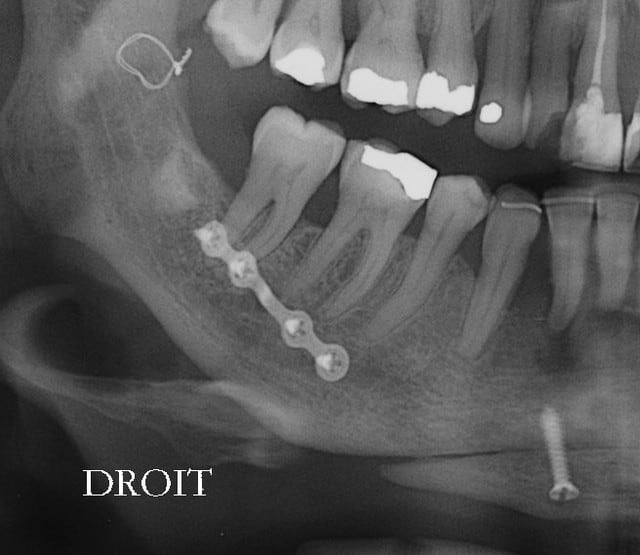

Patiente 58 ans à eu une chirurgie à visée esthétique et "fonctionnelle" adressée pour détartrage en urgence...je ne suis pas spécialiste mais je trouve que la greffe mentonnière est très bof

lésion apicale sur 42 risque de contamination sur la vis en regard..

Plusieurs points: les vis de 15mm x 2mm qui transfixent c'est pas top, une seule plaque, qui plus est non réglable de chaque côté, c'est encore moins top. C'est une plaque de fracture.

En mandibulaire gauche c'est quoi ce fil d'osteosynthese? Un troisième fragment? En laissant l'apex de la 48 pile sur le trait d'osteotomie, je dis chapeau.

Pour la lésion de 42, ca peut être lié à la genio. Forage hasardeux? Mais je vote plus pour une lésion endo/paro

il y a de l'os autour de 11 et 21 ?

On dirait une chirurgie des années 90 :-(